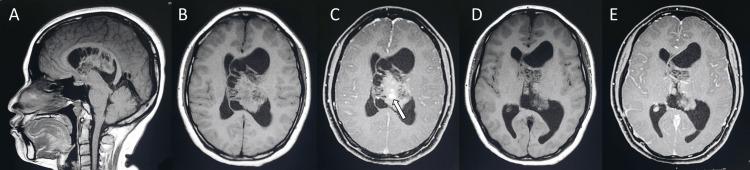

Central neurocytoma (CN) is a rare intraventricular tumor. The common presenting symptoms of CN are headache, vomiting, and visual disturbance, which results from increased intracranial pressure. This report presents a case of CN with unusual clinical presentations. A 25-year-old female with CN presented with a one-day history of unilateral headache, ipsilateral periorbital pain, multifocal paresthesias, and vomiting. Magnetic resonance images showed an intraventricular mass with a soap-bubble appearance and numerous cystic areas typical for CN, causing obstructive hydrocephalus and a midline shift. After one night of rest, her headache, periorbital pain, and paresthesias disappeared. It is possible that the tumor could be mobile with regard to the patient's head position, causing occasional obstruction of the foramen of Monro. Due to the tumor size, which was larger than 4 centimeters, the surgical approach with either gross tumor resection or subtotal resection plus adjuvant radiotherapy should be carefully considered.

中枢神经细胞瘤(CN)是一种罕见的脑室内肿瘤。CN的常见症状为头痛、呕吐和视觉障碍,这些症状由颅内压升高引起。本报告介绍了一例具有不寻常临床表现的CN病例。一名患有CN的25岁女性,有一天的单侧头痛、同侧眶周疼痛、多灶性感觉异常和呕吐病史。磁共振成像显示脑室内有一个呈肥皂泡样外观且有许多典型CN囊性区域的肿块,导致梗阻性脑积水和中线移位。经过一晚休息后,她的头痛、眶周疼痛和感觉异常消失了。肿瘤可能会随着患者头部位置移动,偶尔阻塞Monro孔。鉴于肿瘤大小超过4厘米,应仔细考虑采用肿瘤全切或次全切除加辅助放疗的手术方法。